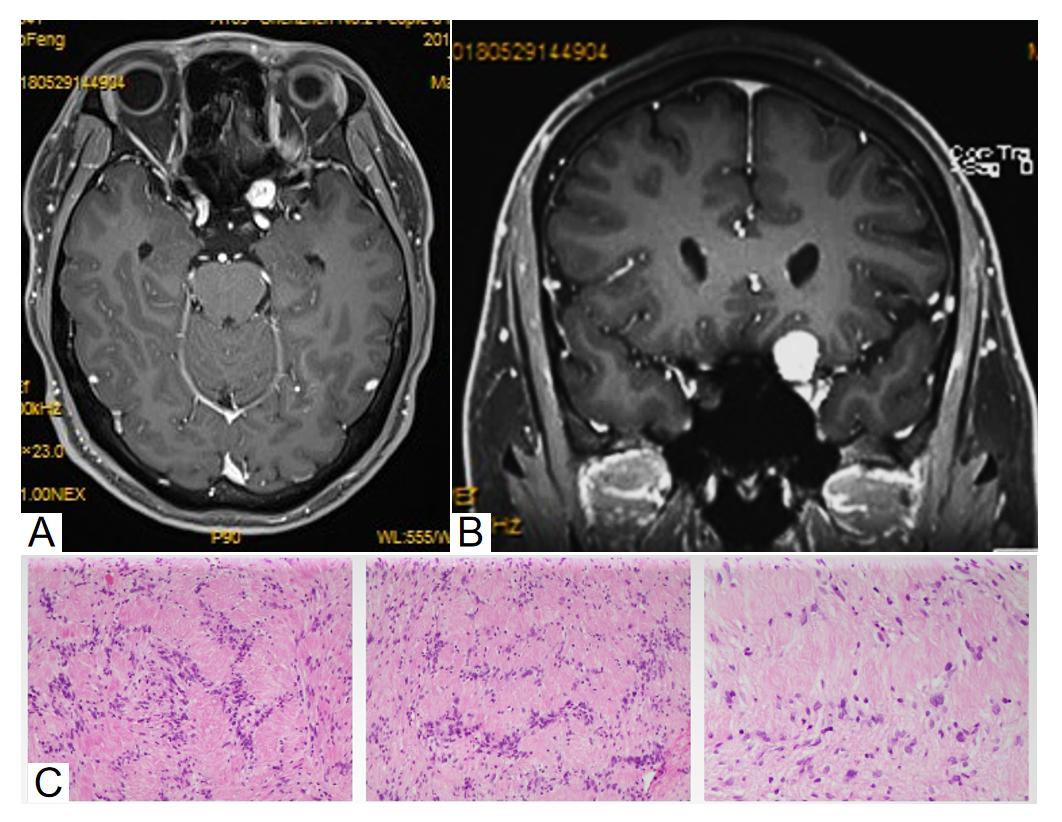

图4 颅脑和眼眶MRI增强序列和病理

Figure 4 Cranial and orbital MRI contrast-enhanced sequences and pathology

(A)为水平位,(B)为冠状位:左侧前床突区左前缘、视交叉前外侧可见类圆形异常信号灶。(C) 病理检查:肿瘤细胞呈漩涡状排列,胞浆丰富,核卵圆形。

(A) Axial view, (B) coronal view: At the left anterior clinoid region and prechiasmatic lateral area, a roundish abnormal signal focus is visible. (C) Pathological examination: The tumor cells exhibit a whorled growth pattern, with abundant cytoplasm and oval nuclei.